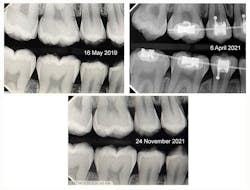

Typical dental soft picks are dipped and coated with SDF solution (figure 1). A bitewing film from May 16, 2019, shows radiolucent changes on the mesial surfaces of both permanent first molars (figure 2, top left). The first dental pick coated with SDF was used at this appointment.

The patient returned for a routine recall appointment on April 6, 2021, wearing fixed orthodontic hardware. A bitewing radiograph was taken (figure 2, top right). The site was cleared with floss, and a new pick soaked with SDF was inserted (figure 3). A small applicator was used to paint sluiceways to enhance the flow of SDF. The pick was slid in and out of the interproximal surfaces a few times (figure 4). The treatment site was immersed in 5% fluoride varnish (figure 5).

The patient returned for a recall appointment on November 24, 2021, 19 months after the initial SDF application (figure 2, bottom).

It’s difficult to standardize contrast on digital bitewing radiographs, so comparative radiolucent changes are equally difficult to interpret perfectly. But in this case, the combination of SDF, daily flossing, initial fluoride varnish, and daily toothbrushing and flossing with a fluoride-containing toothpaste actually “healed” these treated enamel tooth surfaces. The results shown here are typical of what we have observed in patients over the past seven years who are treated with SDF using fluoride dental picks on posterior primary and permanent teeth.